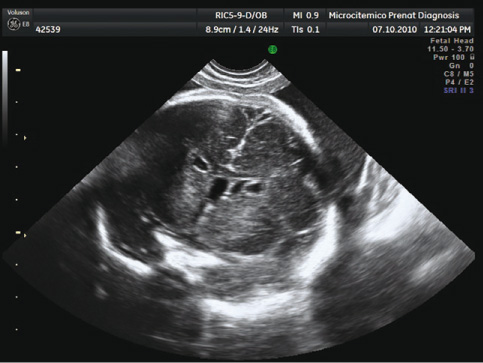

The location of the pseudocysts on axial scans was below the outer edge of the lateral ventricles (Figure 2). The lateral ventricles were symmetrical and of normal size and shape. Other structures, such as orbits, corpus callosum, septum pellucidum, ventricles, thalami, pons, cerebellar vermis, and posterior fossa, were confirmed.

Prenatal ultrasound at 28 weeks plus 4 days obtained by sweeping the three-dimensional volume.

Periventricular pseudocysts were located below the angle of the outer edge of the lateral ventricles in the coronal plane.